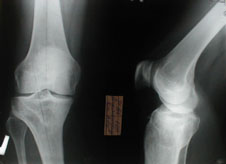

Больная жалуется на боли по медиальной поверхности сустава, клинически варусная деформация, рентгенологически примерно 10 градусная разница по сравнению с левой б/берцовой костью, хотя, допускаю, что причина болей все же повышенная нагрузка в связи с неопороспособностью левой н/к.

МБ> Больная жалуется на боли по медиальной поверхности сустава, клинически

МБ> варусная деформация, рентгенологически примерно 10 градусная разница по

Да, перегрузка тут, конечно, ни к чему. Но мне кажется, тогда нет большой необходимости оперировать обе ноги сразу. Эта-то нога опороспособна уже сейчас, так что лучше сосредоточиться на псевдартрозе бедра.